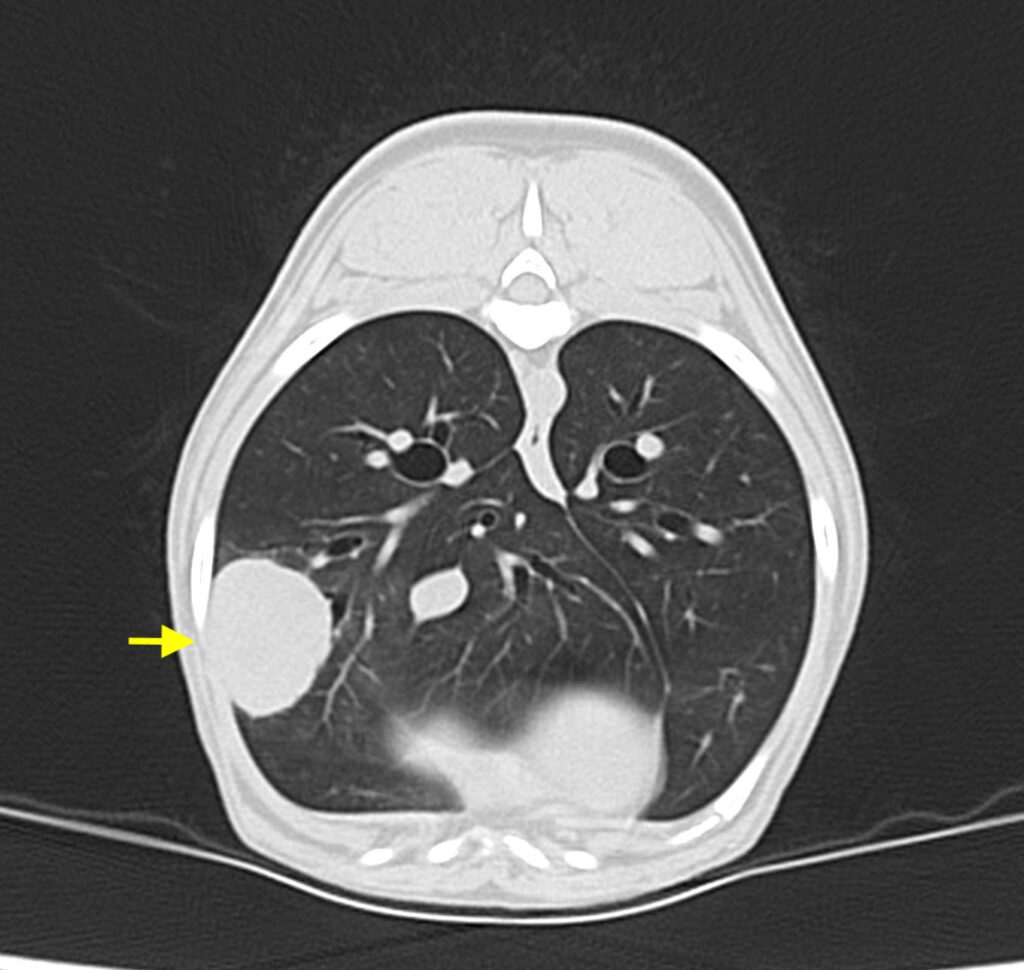

腫瘍の発生部位や転移の有無を精査するため、他院でCT検査を行なってもらい、外科的切除が適応と判断しました。

手術は当院で、肋間開胸術というアプローチ法で腫瘍がある部位の肺葉切除術を実施しました。